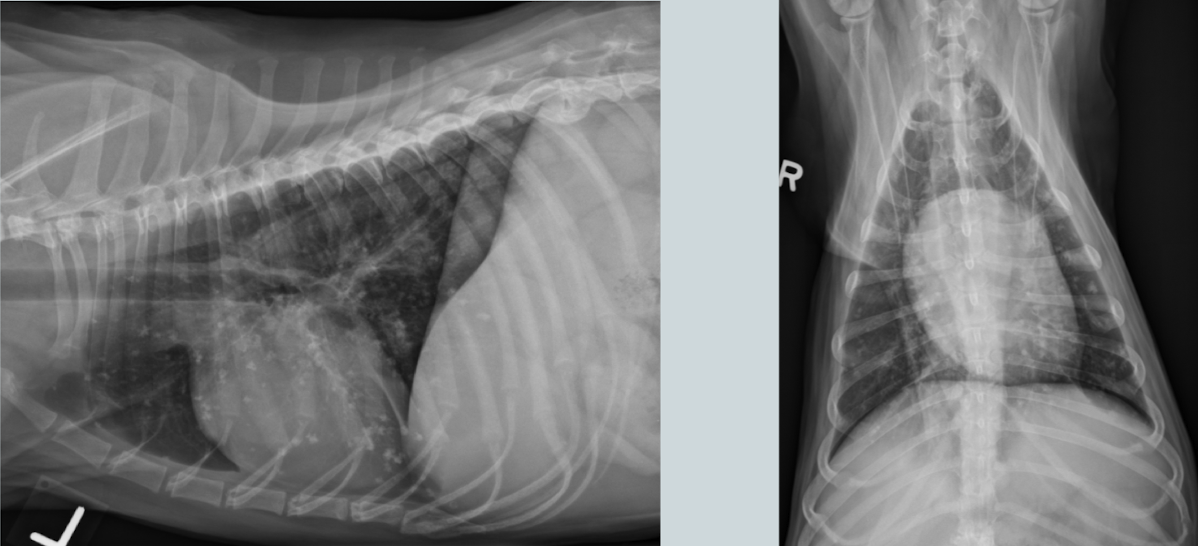

What lung pattern?

Bronchial pattern (see doughnuts)

What lung pattern? What are the arrows pointing to?

Bronchial pattern

tram tracks

Lung pattern?

diffuse severe bronchial pattern

Cat. Likely condition? How do you know?

Feline asthma

flat diaphragm, donuts (bronchial pattern), huge lungs

Condition?

bronchiectasis